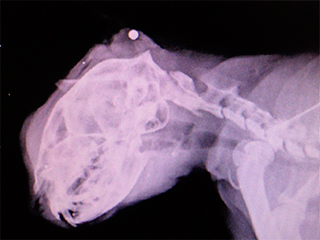

Коту с пулей в голове удалось выжить23 сентября 2014, вторник, 16:14 – БРЯНСК.RU | Комментарии: 0

| Версия для печати Челябинские ветеринары сумели спасти кота с пулей в голове. Неизвестный живодер выстрелил в бездомное животное и пневматического ружья.Несчастное и искалеченное животное обнаружили на улице случайные прохожие. Они незамедлительно принесли его в ветеринарную клинику. Врач первым делом, после осмотра животного отправил его на рентген. Позже когда снимок был готов, выяснилось, что коту чудом удалось выжить, передает LifeNews. В затылочной части черепа животного застряла пуля из автоматической винтовки. Ветеринары тут же приняли решение во что бы то ни было спасти животное. Как после рассказала врач, проводившая операцию, пулю сразу же извлекли, однако животному пришлось перенести не одно хирургическое вмешательство, а целых два. Ему также собрали два перелома нижней и верхней челюстей. Коту-герою дали кличку Киря. Пока он до сих пор живет в клинике для животных, однако волонтеры очень надеются, что в скором времени животное реабилитируется и найдет себе новых хозяев. Как ранее писали Дни.Ру еще одну уникальную в своем роде операцию провели в Краснодаре. Там бездомной кошке по кличке Булочка сделали пластику носа, чтобы облегчить дыхание. У животного были старые раны, которые почти зажили, но сильно беспокоили его, не давая дышать. В процессе операции все лишние ткани были отрезаны, а места разрыва сшиты. Bрачи постарались полностью восстановить нос и нижнюю губу. В республике Коми спасателям удалось спасти кошку, которая просидела на линии электропередач три дня. Все это время она просидела голодной, а когда пыталась спуститься ее было током. Электрикам "пришлось выводить линию в ремонт и спасать мурку". Ее обвязали веревкой и аккуратно опустили прямо в руки хозяев. Во время этой спасательной операции без электричества на некоторое время остались жилые дома поселка. Источник: